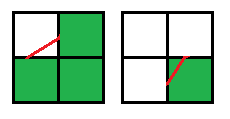

1. Три квадрата одного знака и один противоположного, движение контура происходит по диагонали:

2. Два квадрата одного знака и два противоположного, причем квадраты с одинаковым знаком находятся по одну сторону, движение контура идет вертикально или горизонтально: